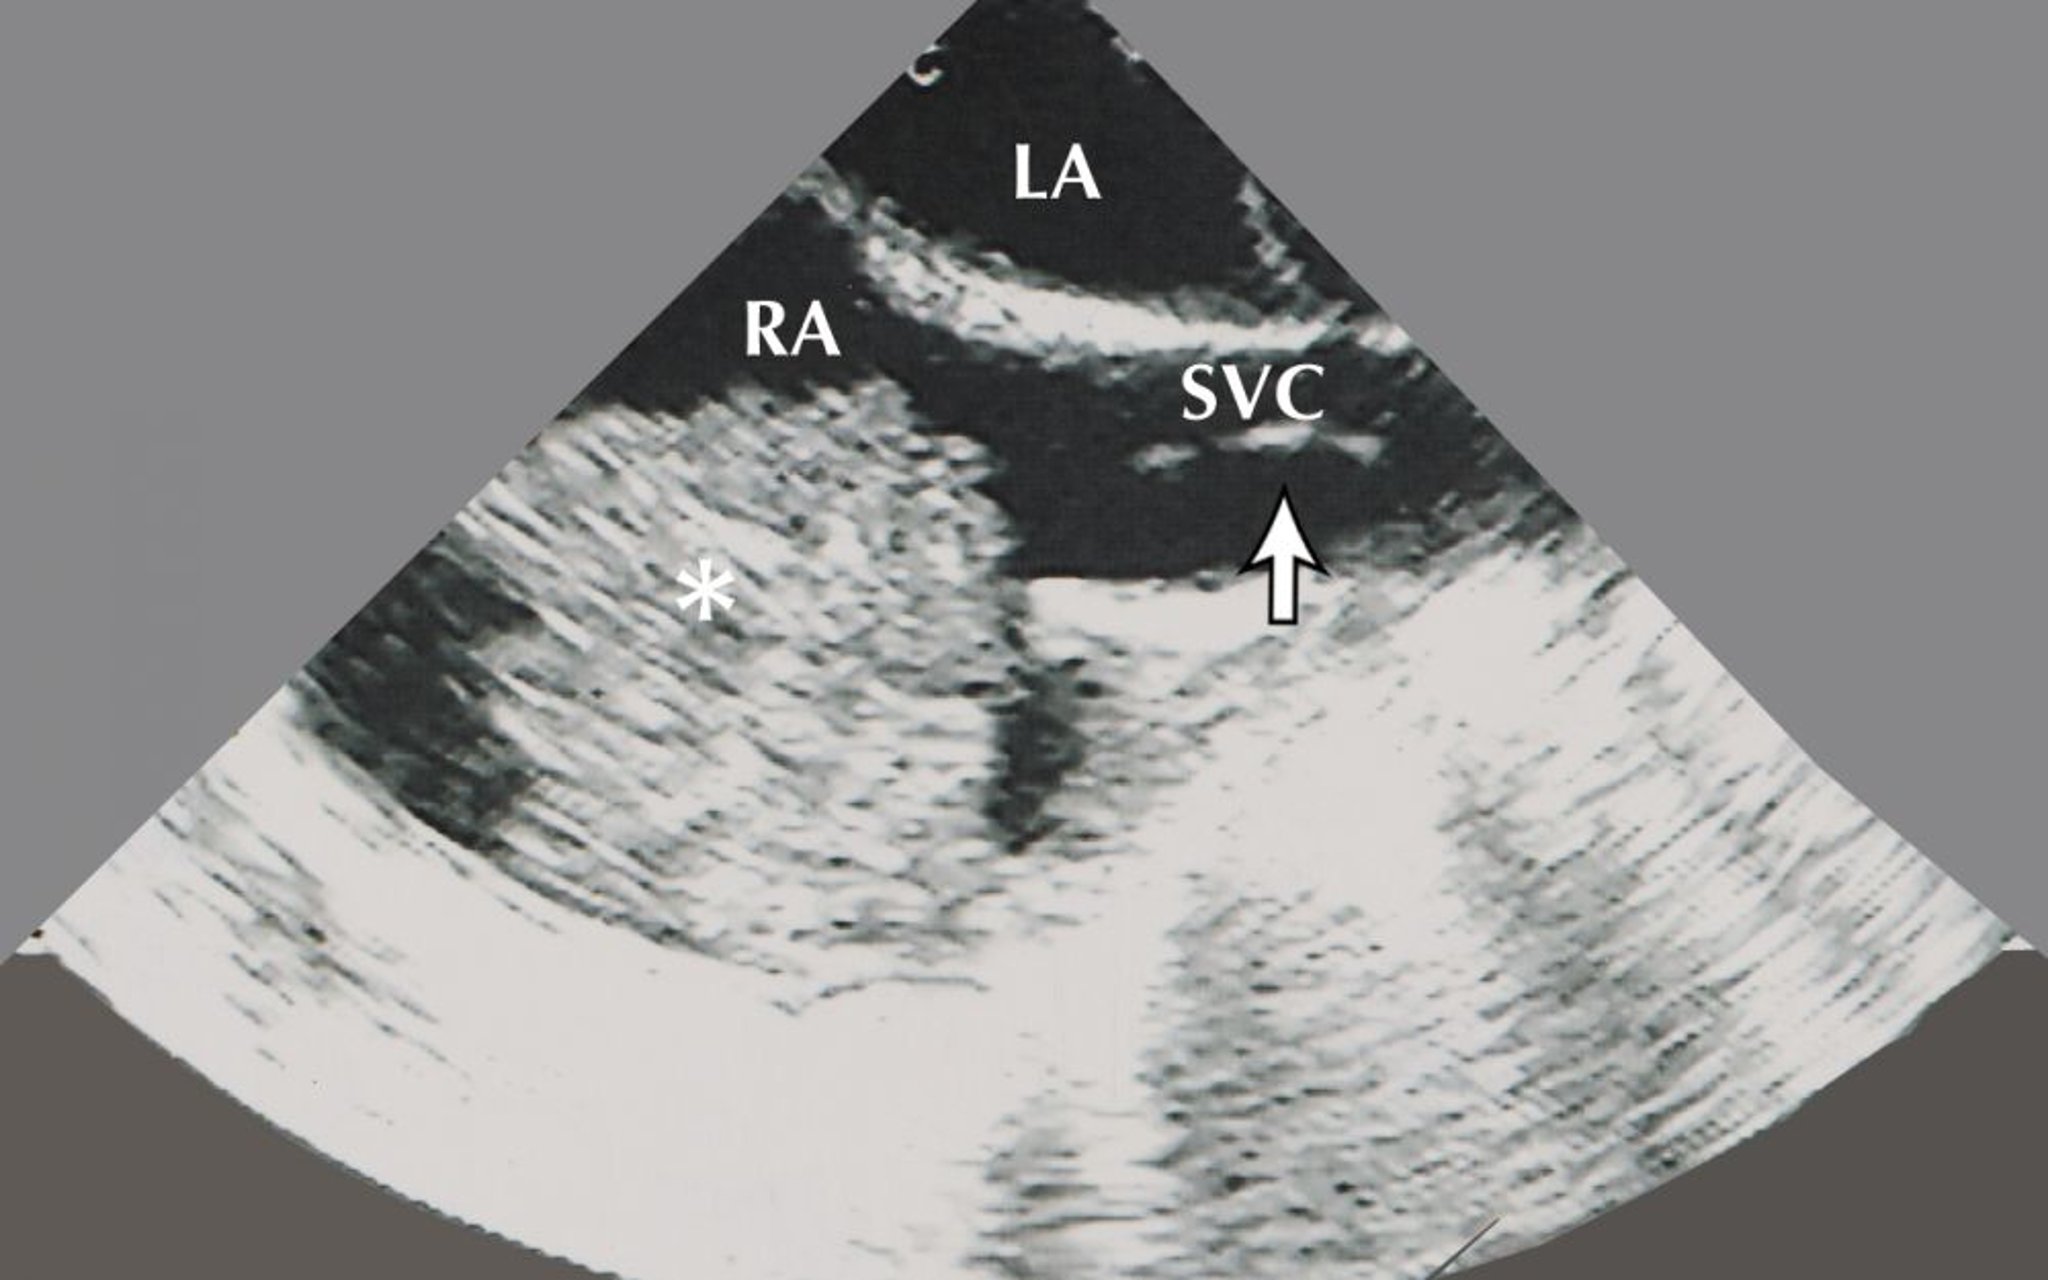

Mixoma atriale (ecocardiogramma)

Questa immagine mostra un mixoma atriale (indicato dall'asterisco) nell'atrio destro. Sono visibili anche su questa immagine ecocardiografica l'atrio sinistro e uno strumento per biopsie (indicato dalla freccia) nella vena cava superiore.